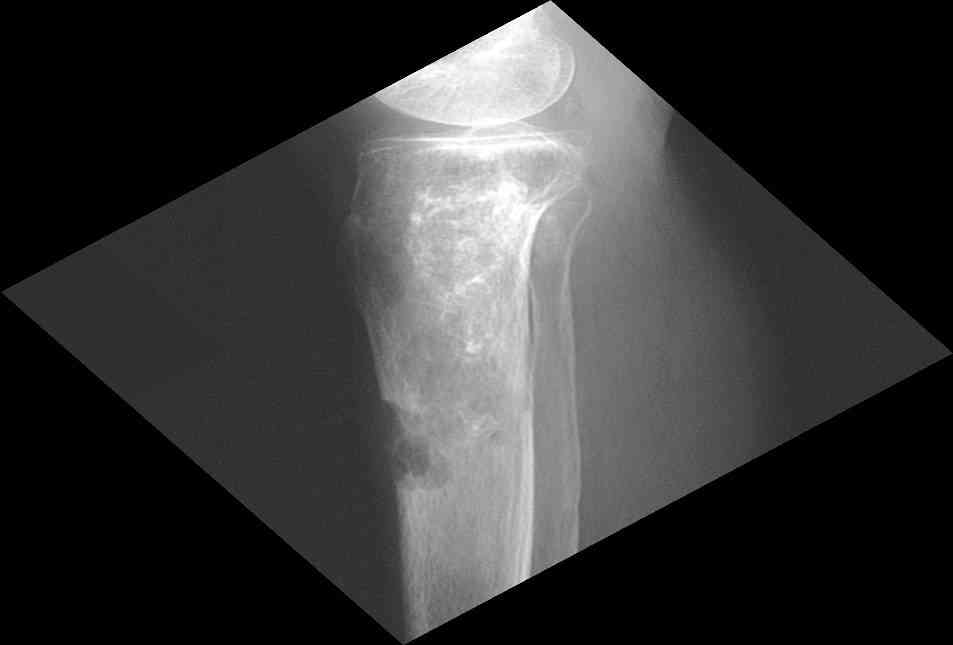

Изменения структуры костей у Вашего пациента больше похожи на полиоссальную форму фиброзной дисплазии или болезнь Педжета, возможены также инфаркты костного мозга б.берцовых костей. К сожалению, качество снимка не очень хорошее, непонятно, сохранен ли кортикальный слой б.берцовых костей по передней поверхности.

Для примера привожу случай из архива американской ассоциации рентгенологов (ACR) - развитие злокачественной фиброзной гистиоцитомы на левой б.берцовой кости у пациента с множественными инфарктами костного мозга (рис 4,5 - левая, рис 6 - правая)

Не являюсь специалистом по костной патологии, но мне кажется, на ренгенограмме множественные мета-диафизарные образования напоминяющее змееподобных извилистых линии и периостеальные ламинирование очень напоминяет картину остеонекроза (инфаркта) костей, возможно связано с длительным применением стероидов.